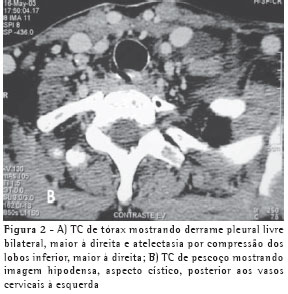

RELATO DO CASOUma mulher de 63 anos, do lar, não tabagista, previamente hígida, apresentou-se com queixa de aumento de volume em pescoço, face anterior do tórax, abdome e membros inferiores. Havia associação com dispnéia discreta aos esforços. O quadro teve início após atividade física leve em academia de ginástica, havia cinco dias. Negava doença pulmonar prévia e referia uso de fluoxetina a 20 mg/dia, bromazepam a 3 mg/dia e reposição hormonal feminina regular. Ao exame clínico observou-se um discreto aumento de volume em fossa supraclavicular esquerda e face lateral direita do pescoço. Observou-se ainda diminuição do murmúrio vesicular de forma difusa e de frêmito toracovocal em bases (direito maior que esquerdo), além de edema de parede abdominal anterior e de membros inferiores (grau I/IV). Foram solicitados hemograma, coagulograma, glicemia, creatinina, uréia, velocidade de hemossedimentação, colesterol total, HDL, triglicerídeos, T3, T4, TSH e parcial de urina, os quais se apresentaram todos normais, descartando a presença de dislipidemia, coagulopatia, infecção, nefropatia e hipotireoidismo. A avaliação radiológica do tórax revelou um pequeno derrame pleural bilateral (Figura 1), confirmado pela tomografia axial computadorizada de tórax (Figura 2A). Esta foi complementada com cortes ao nível do pescoço, que evidenciaram edema na região supraclavicular esquerda com imagem hipodensa (20 x 10 mm) adjacente ao feixe vasculonervoso do pescoço (Figura 2B). A ultra-sonografia da região cervical mostrou a formação de uma coleção cística, posteriormente aos vasos cervicais, sugestiva da ruptura do tronco jugular esquerdo. Demonstrou ainda um pequeno aumento da espessura do músculo esternocleidomastóideo esquerdo, sugestivo de processo inflamatório secundário a distensão muscular (Figura 3). A paciente foi submetida a toracocentese diagnóstica à direita com obtenção de líquido leitoso compatível com QT. A análise laboratorial demonstrou tratar-se de um exsudato com predomínio de polimorfonucleares e com dosagem de triglicerídeos de 2.035 mg/dl, colesterol de 131 mg/dl e proteínas de 9,7 g/dl, confirmando o quadro laboratorial de QT. Foram realizadas citologia oncótica, bacterioscopia de Ziehl, micológico direto e culturas, que resultaram negativos, descartando processos malignos e doenças infecciosas.